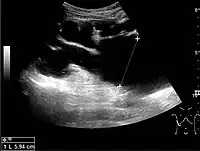

Figure 19. Centrally-located stone with posterior shadowing. No hydronephrosis is present. Measurement of kidney length on the US image is illustrated by ‘+’ and a dashed line.[1]

With US, larger stones (>5–7 mm) within the kidney, i.e., in the calyces, the pelvis and the pyeloureteric junction, can be differentiated, especially in the cases with accompanying hydronephrosis (Figure 18 and Figure 19). Hyperechoic stones are seen with accompanying posterior shadowing. Additional twinkling artifacts below the stone can often be seen using Doppler US. Large stones filling the entire collecting system are called coral stones or staghorn calculi and are easily visualized with US (Figure 20). Stones in the ureters are usually not visualized with US due to the air-filled intestines obscuring the insonation window. However, ureteral stones near the ostium can be visualized with a scan position over the bladder. An exam of the ureteric orifices and the excretion of urine to the bladder can be performed by inspecting the ureteric jets in the bladder with color Doppler US.